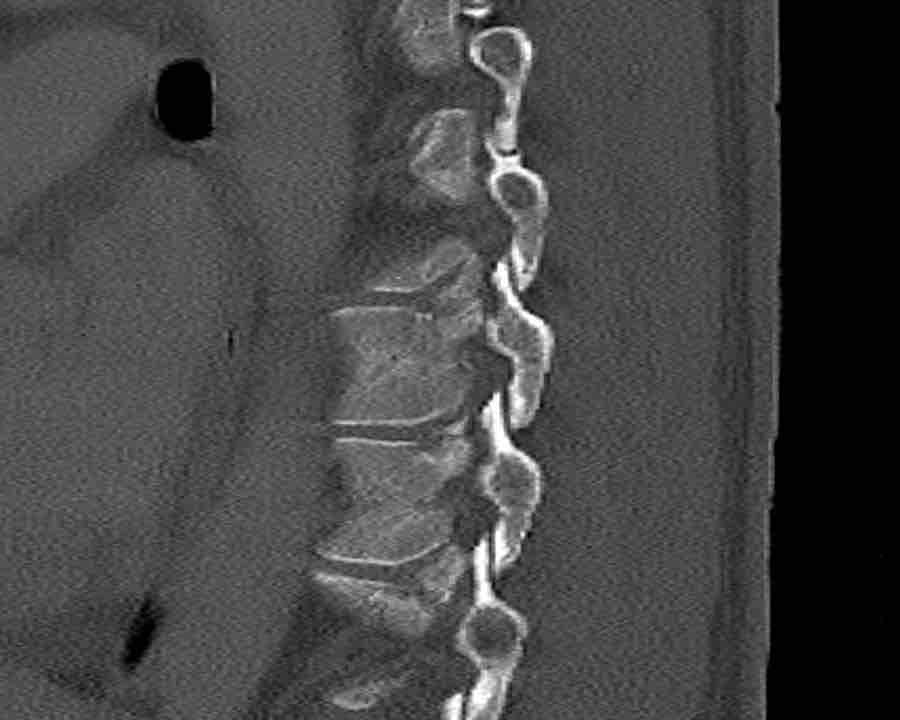

Findings

- Black arrows: horizontal fractures through the pedicles as a result of flexion distraction trauma.

- White arrows: soft tissue swelling indicating injury to posterior ligaments.

- Circle: compression fracture of posterior wall (2 points) and two endplates (2 points)

Conclusion

Type B2-A4

Flexion distraction injury with separation on the posterior side and a secondary burst fracture involving both endplates and the posterior wall.